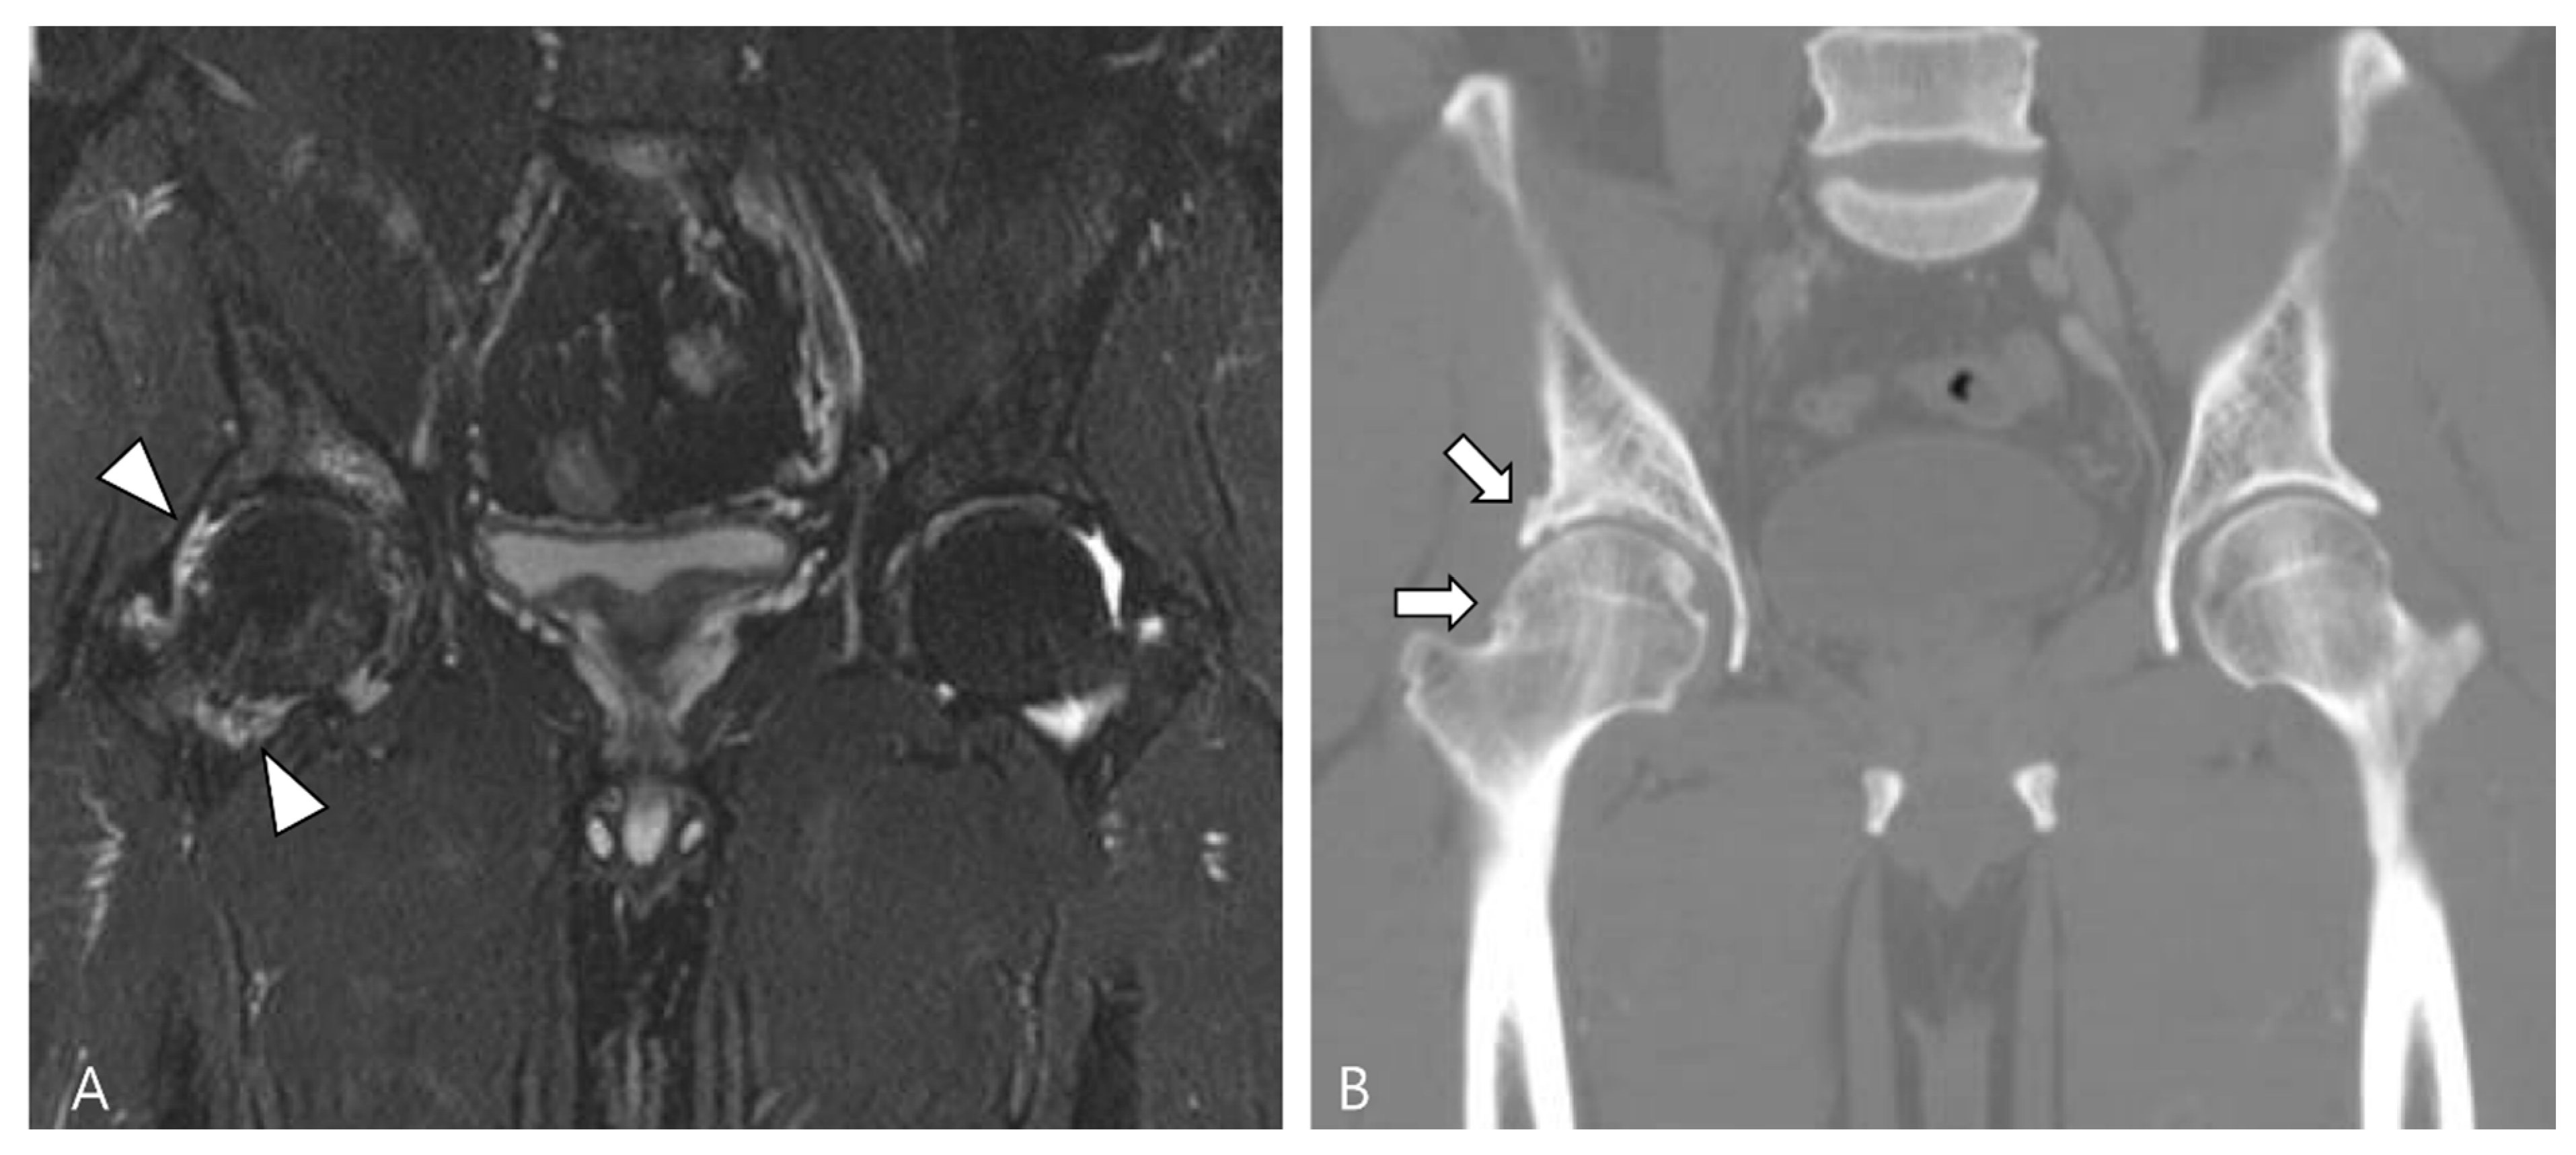

2.4. Relationship to Adjacent Structures of D-TSGCT

3.1. Differential Diagnoses of Intra-Articular D-TSGCT

3.1.1. Hemosiderotic Synovitis